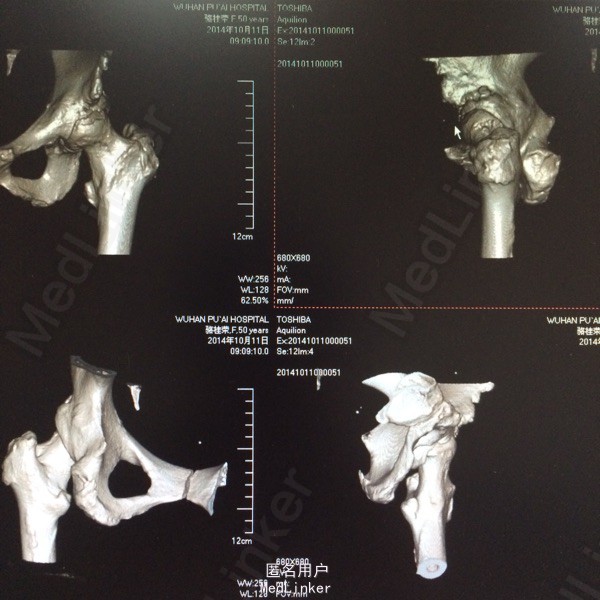

患者,女,50岁。因“双髋关节疼痛活动受限一年余”入院。 患者一年余前无明显诱因感双髋关节疼痛,活动后症状加重,休息后稍有缓解,不伴发热、咳嗽,否认明确外伤史。于今年8月在我院门诊拍片(M00085020)示:双侧股骨缺血性坏死。今为求进一步治疗来我院求诊,门诊查体阅片后以“双侧股骨头缺血性坏死”收住我科。 自起病以来,患者饮食睡眠可,二便正常,体力下降,体重无明显改变。 既往:否认肝肾病史,否认食物、药物过敏史

体格检查:T 36.8℃ P 78次/分 R 20 次/分 BP 142/96mmHg,神志清醒,平静面容,扶拐跛行步入病房,查体合作。发育正常,全身皮肤未见黄染,浅表淋巴结未及肿大,头颅无畸形,双侧瞳孔等大等圆,光反射灵敏。颈软,胸廓无畸形,双肺呼吸音清晰,未闻及干湿性啰音。心律齐,各瓣膜听诊区无杂音。腹平软,无压痛反跳痛,脊柱无畸形,各棘突无压痛。双上肢正常。 专科情况:双髋关节未见明显肿胀,腹股沟中点处深压痛,下肢无轴向叩击痛,双髋关节活动度因疼痛减小,4字征阳性,双足背动脉搏动可及,各趾感觉、活动正常,直腿抬高试验阴性,双下肢无明显短缩。 门诊资料:我院MRI(M00085020)示:“双侧股骨头缺血性坏死”。

初步诊断:双侧股骨头缺血性坏死 鉴别诊断:X线片上未见骨肿瘤,骨囊肿等征象可与肿瘤相相鉴别,具体有待于进一步检查。 诊疗计划:1.卧床休息,暂不负重,对症支持处理。 2.完善相关检查(血、尿分析、肝肾功能、骨盆平片、髋关节CT、胸片ECG、心脏彩超等)。 3.择期手术治疗(髋关节置换术)。